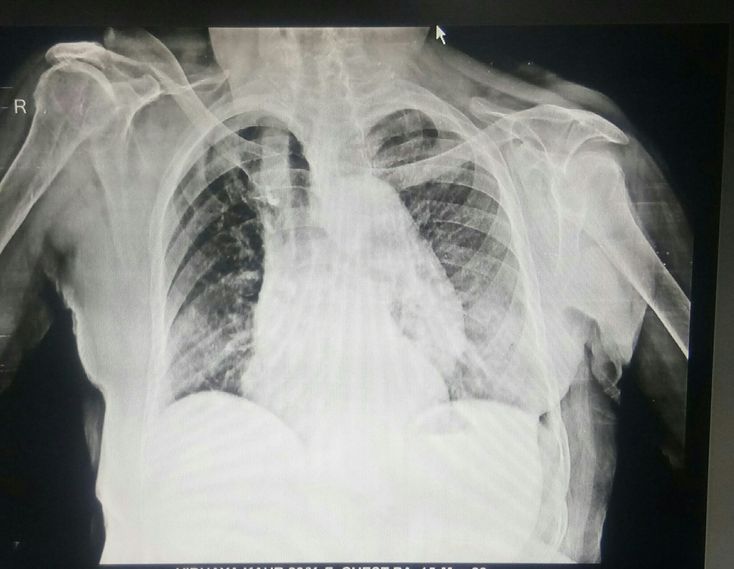

Pneumonia and aortic dissection

Aortic aneurysm